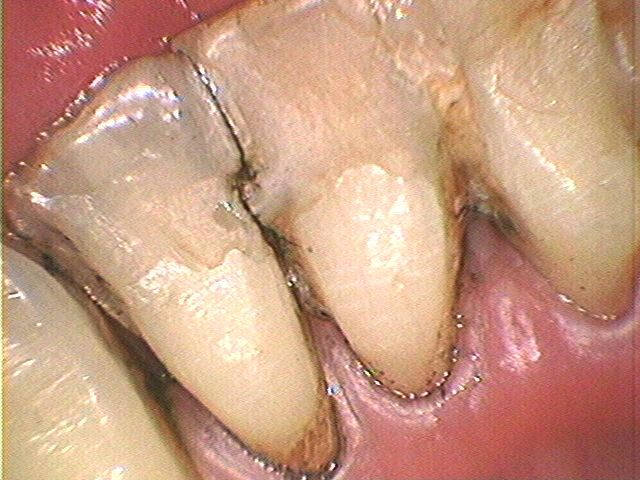

仮固定の効果

しかし、仮固定と共に歯周ポケットの「病原菌除菌」とレーザー治療などによる歯周組織の「ダメージ回復」を統合的に実施しますと短期間で病状が改善し咀嚼も普通にできるようになっています。(Photo.4-1, Photo.4-2)

手遅れの仮固定はすぐに破損する

歯周病第3度になってからの【手遅れ仮固定】では頻繁に接合部が破折致します。(Photo-6,Photo-7)再三の仮固定は給付外ですので、その都度、自費負担となります。さらに仮固定の材料では強度不足ですので病状の進行を防止するためには本格的な長期にわたって動揺歯を固定する装置(咀嚼力分散装置)が必要になります。